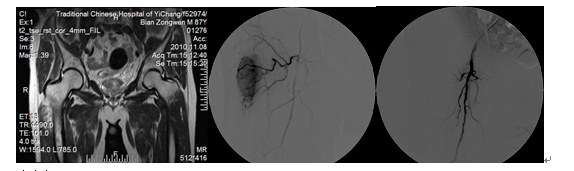

病例三

女、宫颈癌盆腔广泛转移腹部剧烈疼痛,在我院采用中药制剂结合介入盆腔内肿瘤血管灌注术后,肿瘤血管闭塞,疼痛明显减轻,睡眠改善。